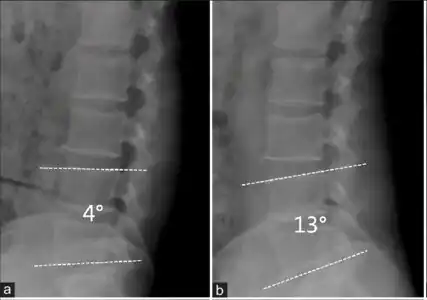

L5 S1 Spondylolisthesis Grade II with forward slipping of L5 on S1 <50%